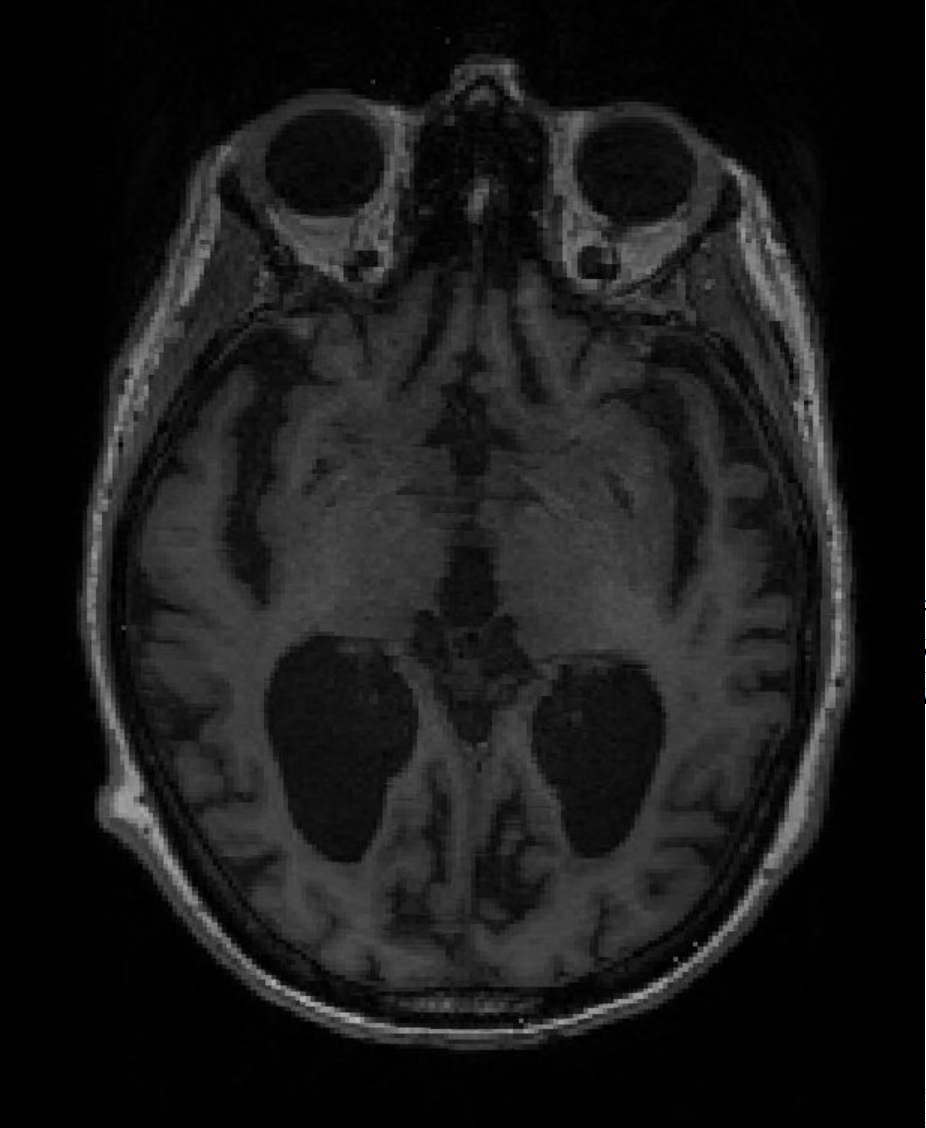

МРТ головного мозга здорового добровольца (Источник: Тимоти Риттман)